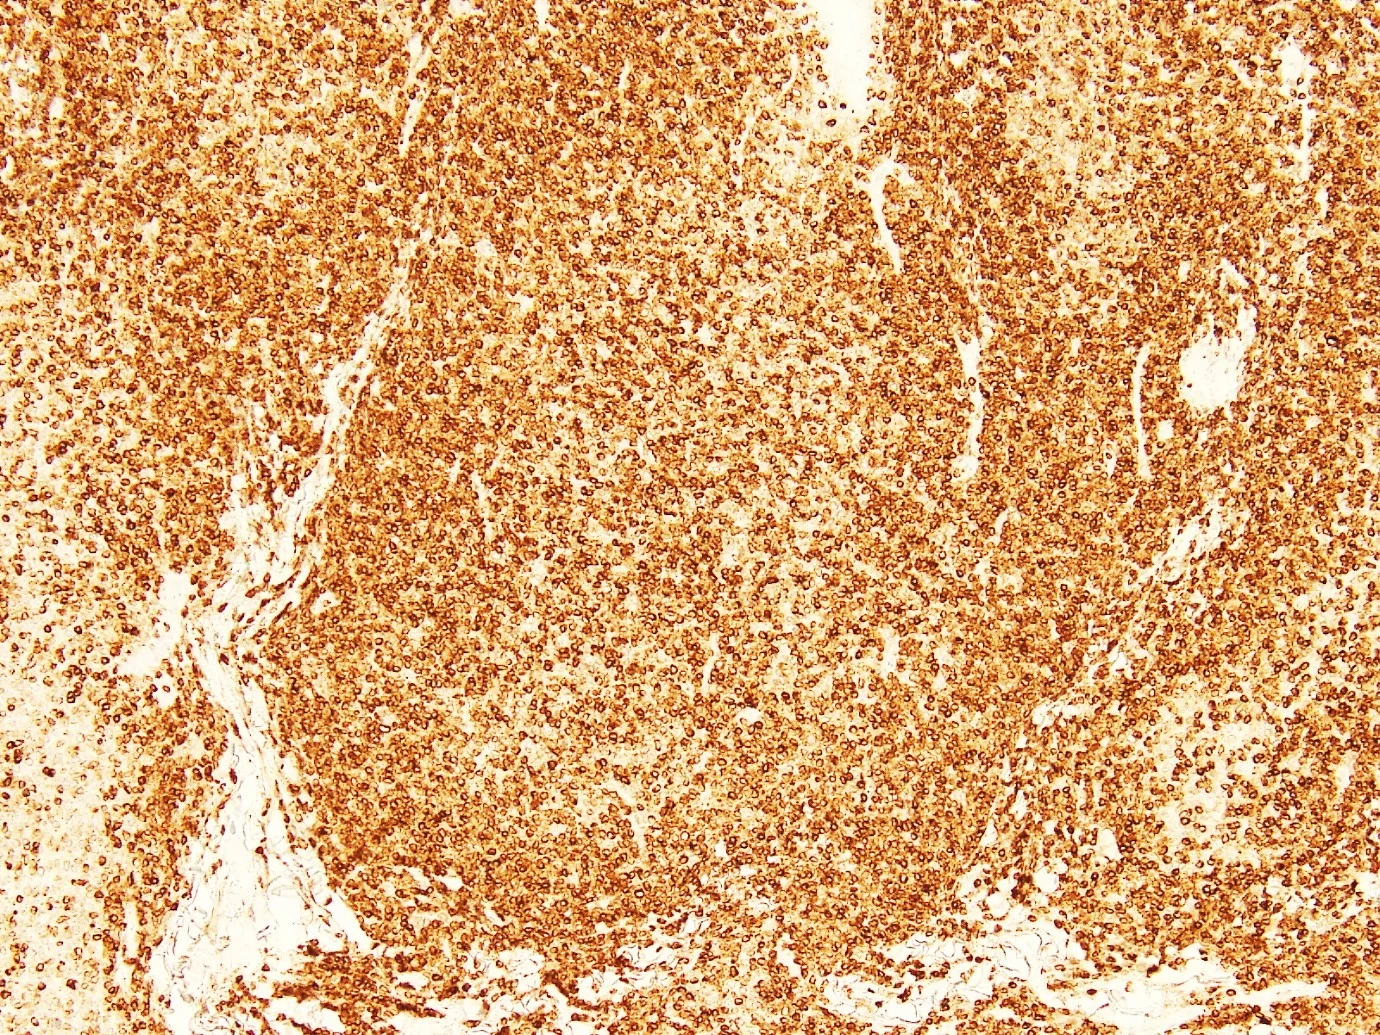

CD20

CD21

D10

BCL2

BCL6

CD79a